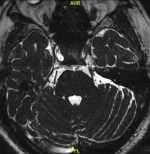

腰部外傷后雙下肢活動障礙、二便失禁患者一例 現(xiàn)病史【一般資料】男性,54歲,農(nóng)民【主訴】腰部外傷后出現(xiàn)雙下肢活動障礙、二便失禁1個月?!粳F(xiàn)病史】患者自訴緣于1個月前腰部外傷后雙下肢活動障礙,不能行走,二便失禁,到青龍縣醫(yī)院住院治療,診斷為“腰椎骨折,腰髓損傷”,行腰椎骨折內(nèi)固定術(shù)治療。目前患者雙下肢活動不利,二便失禁,遂入我科行康復(fù)治療。【既往史】體質(zhì)尚可。否認“結(jié)核、肝炎”等傳染病史,否認“高血壓、糖尿病”等病史,否認藥物和食物過敏史,無外傷及重大手術(shù)史,預(yù)防接種史不詳。【查體】T:36.6℃ ,P:69次/分,R:17次/分,BP:12...